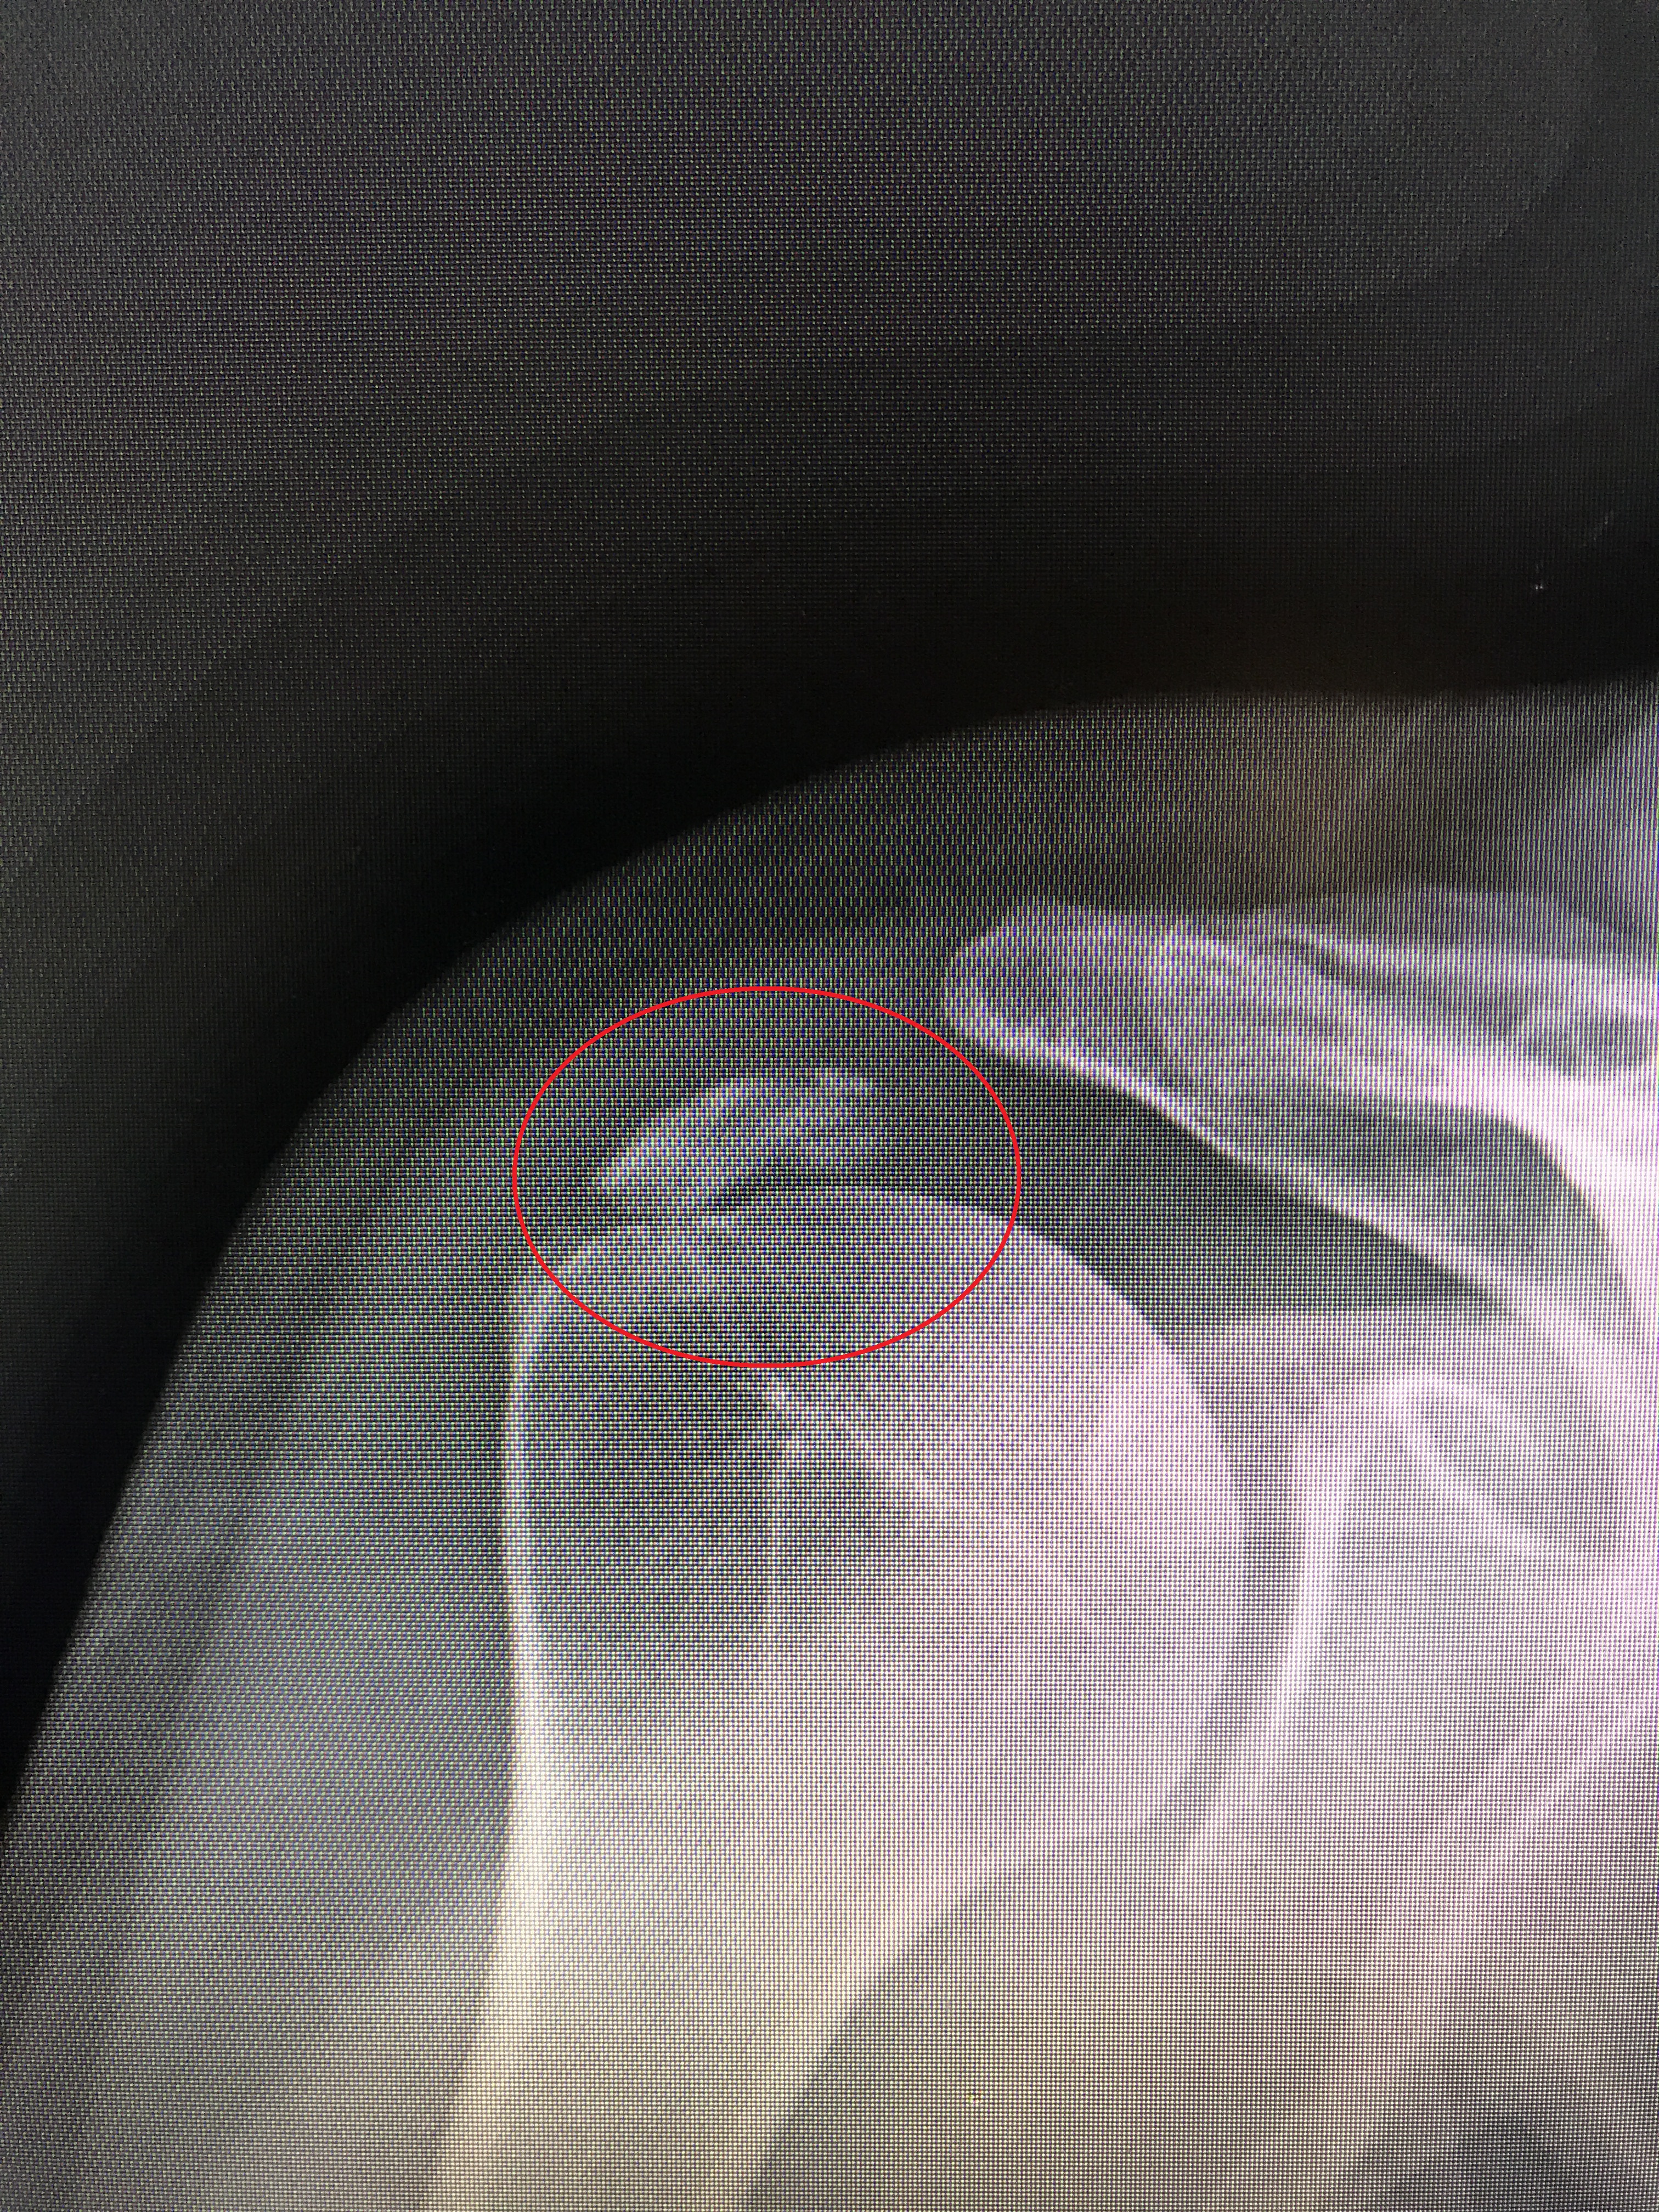

Not knowing any doctors in Charleston, we talked to our daughter and she recommended hers. Since we are here for a long stretch of time I was able to get Lee an appointment and last month he went to see her. The point of the appointment was to transfer his medical records to her and since Lee was also having pain in his right arm that was unusual he decided to talk to her about that. She sent him to get a couple of X-rays and they discovered calcium deposits on his shoulder. Lee specifically stated he did not want to take any kind of an addictive narcotic for the pain, and she said that was fine she would call in a prescription by the end of the day that should help. She also referred him to an orthopedic specialist.

After calling twice, the next day he learned that she was refusing to call anything in because of his heart condition. She was being ultra cautious because of the other medications he was taking. The ortho appointment was also in three weeks. At this point Lee’s pain level was very serious. He was only getting about 2-3 hours of sleep each night, and the pain was pretty intense and constant. He didn’t feel he could wait three weeks and by changing the doctor was able to get an appointment in a few days. In the meantime, we did some research and learned that he didn’t just have a calcium deposit but a bone spur.

Some doctors won’t treat family, and we would have totally understood if he didn’t want to, but Eddie understands how difficult this is with our travel and has first hand knowledge of the sub par care we have often received. In this case, he was surprised (but not surprised) that the standard course of treatment wasn’t done and validated once again that for some doctors there is a bias against higher risk, transient patients. Lee and Ed talked through the best course of action and ultimately decided Lee would drive the eight hours to Columbus and get a cortisone shot. While he was there, Eddie would try to get an MRI scheduled so they could see how much damage was being done. Once he saw the picture of the Xray, Ed was VERY concerned about the size of the bone spur and said that if left untreated there was a chance Lee could permanently lose function in that arm.